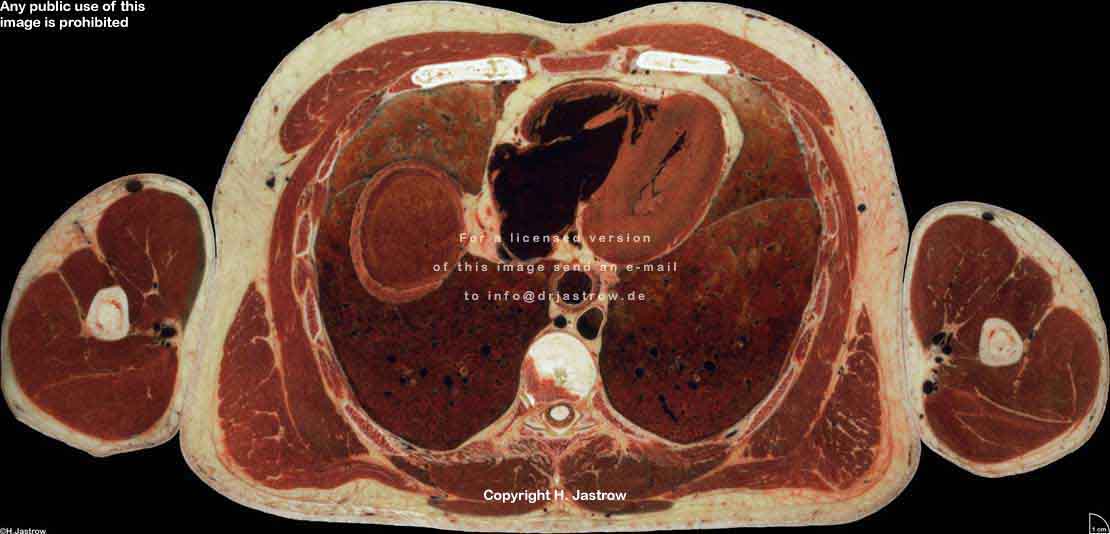

Visible Human male: Sectio transversalis 1464

CT

NMR

Pd                          / T2 \                         T1